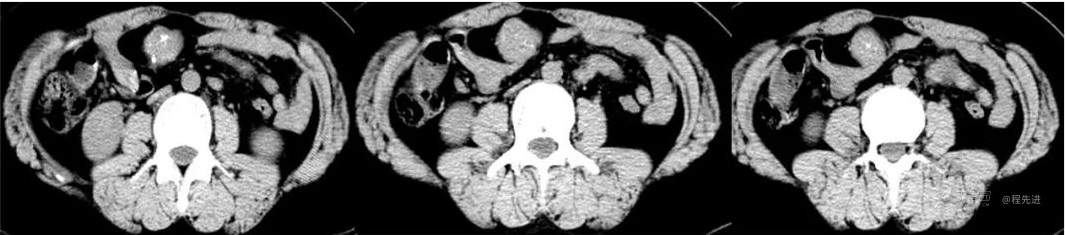

CT

图像依次为平扫(CT值46HU),动脉期(CT值138HU),静脉期(CT值137HU),延时期(CT值96HU)斜矢状位重建